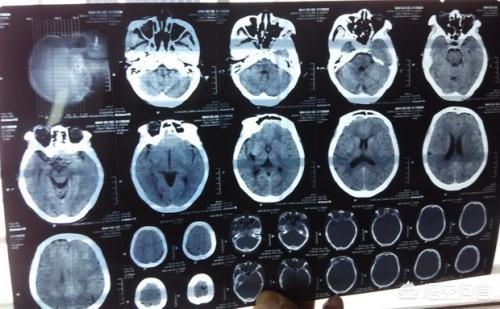

- しかし、臨床像の違いに加えて、時に臨床症状だけでは診断はできないまた、以下のような画像検査も行う。頭蓋CTと頭蓋MR.ラクナ梗塞にせよ脳梗塞にせよ、脳組織が虚血・低酸素状態にあるだけで、梗塞脳組織の液状化壊死はないため、24時間以内の頭部CTでは大きな変化はない。24時間以内であればある程度判別可能である。症状の急性期には、臨床では頭蓋MRが検査の第一選択となる。 MRIには様々なシーケンスがあり、症例によって異なるMRIシーケンスを用いて適切な検査を行うことができる。脳梗塞の診断において、DWIシーケンスは状況を明らかにするのに非常に直感的である。。

(3)検査:頭部のCT検査または核磁気検査。核磁気検査が最もよく、脳の対応する部分に空洞病巣を見つけることができる。

脳出血と脳梗塞は症状が同じであり、症状から判断することはできないので、脳梗塞とラクナ脳梗塞の診断は、脳CTや脳MRIでさらにはっきりさせる必要がある。